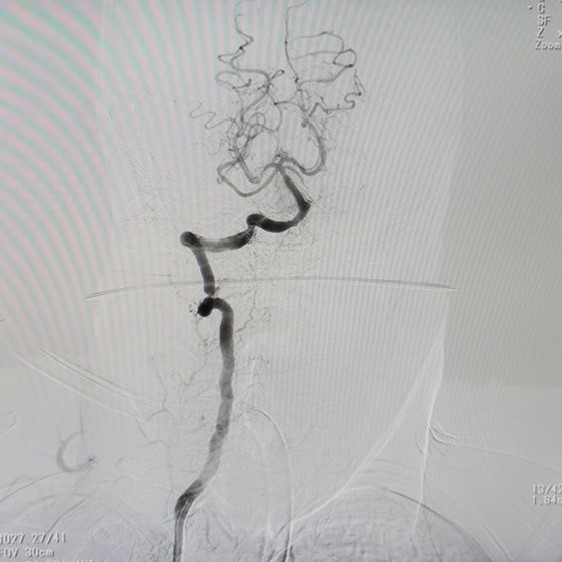

May mắn, các bác sĩ đã kịp thời đánh giá vùng nhồi máu vẫn còn cứu vãn được các tế bào não nên bệnh nhân được chỉ định tiêm thuốc tiêu sợi huyết giúp làm tan cục máu đông – nguyên nhân làm tắc nghẽn mạch máu não. Trong quá trình tiêm, bệnh nhân được chụp phim CTA để khảo sát mạch máu, ghi nhận tắc động mạch thân nền.

Hình ảnh phim CTA của bệnh nhân bị “đột quỵ thức giấc”

Đứng trước tình trạng nguy cấp vì diễn tiến bệnh có thể trở nặng bất kỳ lúc nào, các bác sĩ đã khẩn trương tư vấn và thực hiện phương pháp can thiệp mạch lấy huyết khối để tái thông mạch máu cho bệnh nhân.

Dưới ánh đèn phòng mổ, sinh mạng bệnh nhân đang nằm trong tình trạng nguy kịch và cần sự can thiệp tức thì. Trong khoảnh khắc sinh tử ấy, mỗi giây phút trôi qua đều quý giá, với sự khẩn trương, chính xác và tập trung cao độ, các bác sĩ đã thành công hút và kéo huyết khối cho bệnh nhân, mang lại tiếng thở phào nhẹ nhõm cho cả ekip. Sau khi các mạch máu não được tái thông hoàn toàn bệnh nhân được tiếp tục chuyển sang phòng Hồi sức tích cực để theo dõi và chăm sóc.